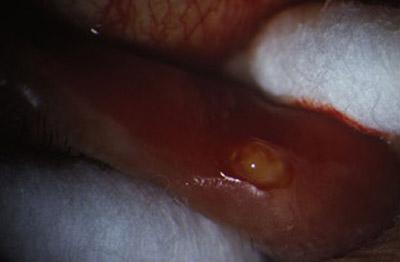

La presencia de un canalículo superior o inferior eritematoso, turgente, a veces doloroso, lleno de abundante material purulento caseoso, de color verde claro, caracteristicamente producido por estos microorganismos, nos lleva al diagnóstico.

El punto lagrimal inferior puede estar vertical, en un ligero ectrópion medial. Al realizar presión sobre el canalículo afectado entre dos hisopos de algodón, y repitiendo esta maniobra varias veces en la lampara de hendidura, se puede obtener abundante material caseoso sin dificultad.